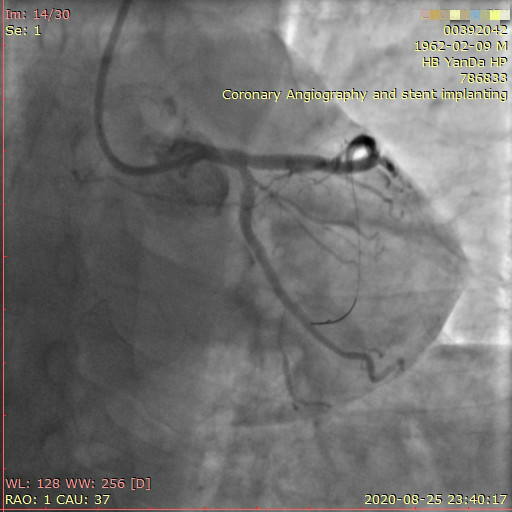

李先生足位術(shù)前影像

李先生足位術(shù)后影像

手術(shù)方案確定之后,在心血管內(nèi)三科趙景新主任、介入醫(yī)學(xué)科富孝晨主任的配合下,翟光耀主任親自擔(dān)任主刀,分別依次對(duì)李先生的三支動(dòng)脈進(jìn)行了完全血運(yùn)重建。由于手術(shù)進(jìn)展順利,李先生術(shù)中沒(méi)有任何癥狀,耐受良好,于是成功的將三支動(dòng)脈“一站式”治療!術(shù)中,由于李先生左主干遠(yuǎn)端分叉處存在嚴(yán)重病變,翟光耀主任選擇國(guó)際指南推薦的DK-mini-Crush技術(shù),確保了分叉處兩支主干開(kāi)口均萬(wàn)無(wú)一失。據(jù)悉,DK-mini-Crush技術(shù)是目前冠脈分叉病變領(lǐng)域最為復(fù)雜及難以掌握的介入技術(shù)之一,對(duì)手術(shù)醫(yī)生經(jīng)驗(yàn)、體力均提出了極大的挑戰(zhàn)。極為擅長(zhǎng)復(fù)雜介入技術(shù)的翟光耀主任卻用嫻熟的技術(shù)確保了李先生手術(shù)的成功。